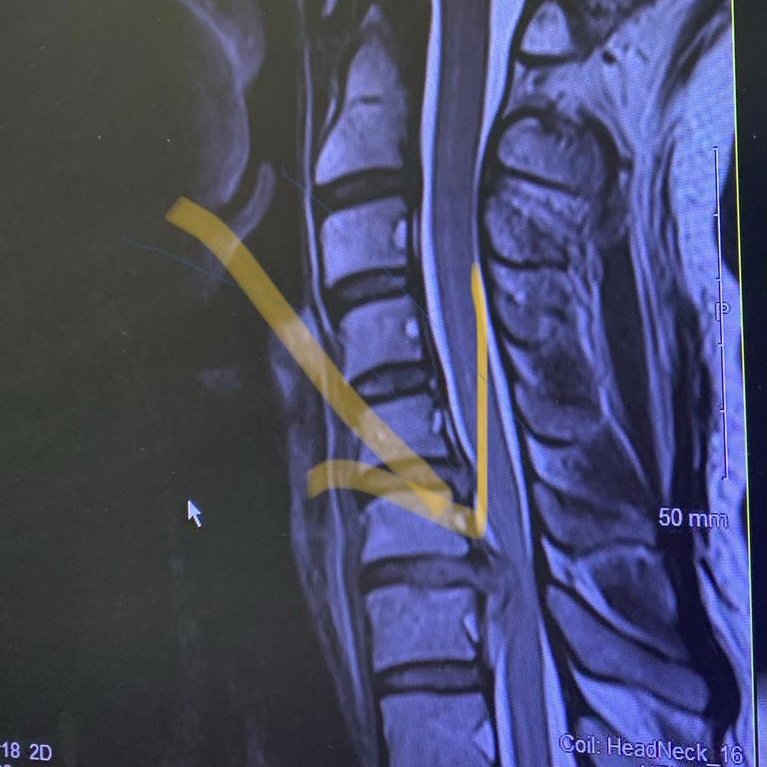

Patient calls. Anxious, symptoms worsening. Now difficulty rising from chair. Arrange consult with private neuro colleague, and she is seen urgently. MRI confirms large prolapse and cervical cord compression. Immediate surgery arranged. Patient recovering well 6/52 post 5/

Insights: 1. Be an advocate for patients. Safety net them. Particularly those who are falling through cracks or incompetencies in the system. I give my number to patients I’m concerned about. They don’t tend to use it unless they need to. But it’s an invaluable saftey net. 6/